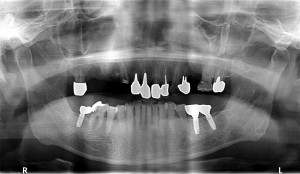

50歳代男性右下7番から左下5番まで欠損。

CTを拝見すると骨幅、骨の高さ十分ありましたので

スイス製ストローマンインプラントRNを8本埋入させて頂き、

即時に仮歯を作成し、装着させて頂きました。

2ヶ月後には、最終補綴物をセットする予定です。